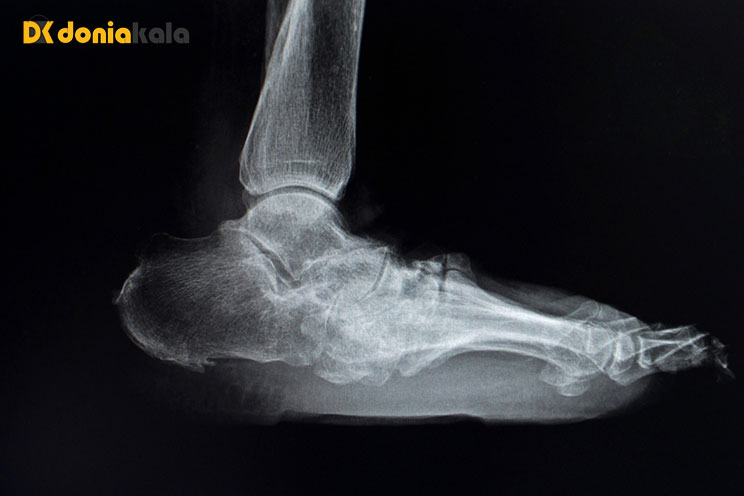

پای شارکو چگونه تشخیص داده می شود؟

در مراحل اولیه تشخیص پای شارکو دشوار است. اشعه ایکس اغلب طبیعی است. اگر اشعه ایکس و تست های آزمایشگاهی طبیعی باشد، پای شارکو با دانستن علائم بیماری تشخیص داده می شود. پای شارکو در افرادی که دیابت و نوروپاتی محیطی دارند و علائم زیر مشکوک است: پای قرمز، داغ و متورم (بدون زخم پا) و افزایش دمای پوست در پای آسیبدیده (در مقایسه با پای دیگر).